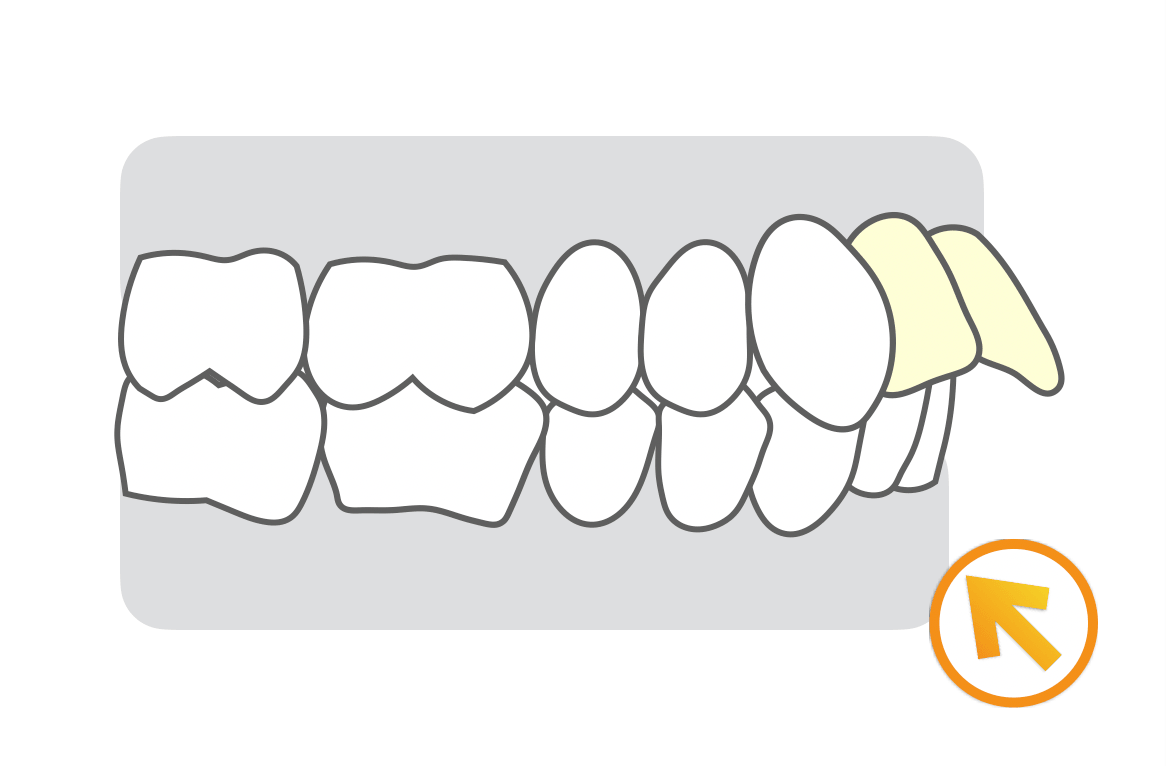

①上顎遠心移動方針

上の歯列全体を後方移動させます。主に上の歯並びが大きく前方に傾斜していないケースが適応となります。治療成功率はやや低めになります。

強い固定源を必要としますので、歯科矯正用アンカースクリューを併用することが多いです。マウスピース型矯正治療ではII級ゴムという上下のゴムを使用して改善します。まだ生えていなかったとしても治療開始前に上の親知らずを抜歯しておかなくてはなりません。